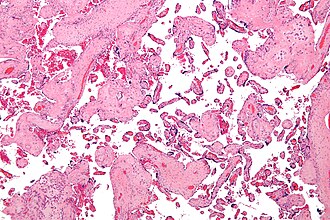

Placental villous immaturity. H&E stain. | |

| LM | Increased numbers of intermediate villi (in relation to the gestational age) - increased vascularity and more central vessels, edema, +/-macrophages, less mature terminal villi |

- Increased numbers of (immature) intermediate villi (in relation to the gestational age) with:

- Increased number of capillaries.

- Edema.

- Macrophages.

- Large diffusion distance (vessel-to-villous surface distance large).

- Less (mature) terminal villi.[4]